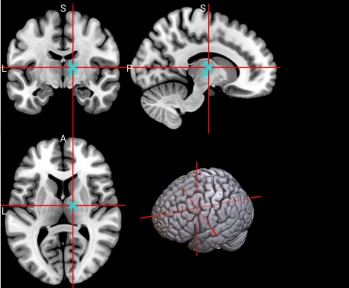

33,

34

L & R Insula (INS)

The insula has many functions including sensorimotor processing, emotion and decision making, attention and salience processing, and speech [64].

/word/media/image13.png/word/media/image13.png